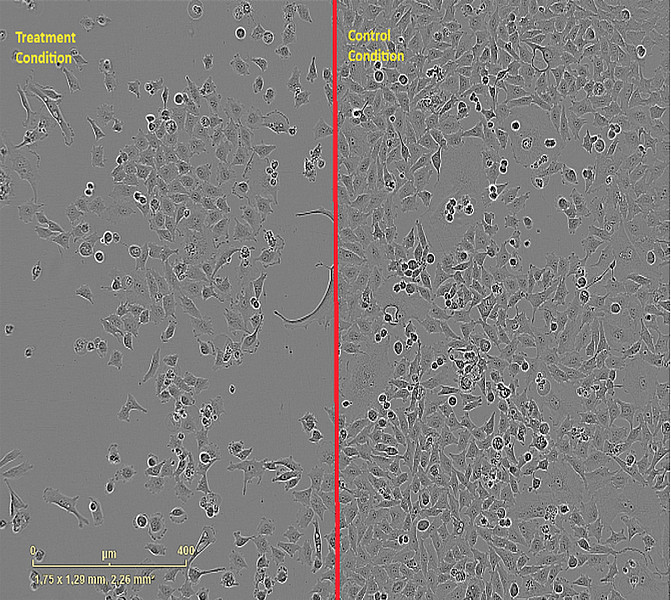

Drug response profiling (DRP) - Treatment response in cancer is influenced by multiple biological factors including genetic alterations of tumor cells and the tumor microenvironment. To investigate modulators of therapy response in patients, we can model drug response ex vivo. For this, we isolate primary tumor cells from peripheral blood or diagnostic biopsies and treat them with a large library of clinically available and experimental drugs.

Additionally to important biological findings, ex vivo DRP can be used to predict the response of individual patients beyond known markers of therapy resistance. Based on this readout, we were able to treat patients who lacked any further standard treatment options.

Live Cell Imaging - This project involves a collaborative effort with the Chair in Algorithmic Bioinformatics to characterize the dynamic response to drugs using a live-cell imaging-based detection and computational modelling approach.